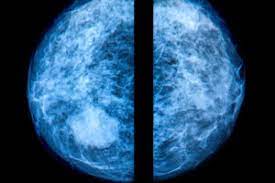

Mammography is the most effective screening tool to detect breast cancer, especially among women 40 and older. In cancer screening, a negative result means no abnormality is present. 3d mammograms and breast mris are two of the best ways for your healthcare team to keep a close watch on any breast changes or abnormalities. The average size of breast cancer, when found on mammograms, is 1.1 cm. Health, united states, 2019, table 33.

Overall, screening mammograms miss about 20% of breast cancers that are present at the time of screening. It is one of the leading causes of cancer mortality among women in the united states. It said 1 million women. 3d mammograms and breast mris are two of the best ways for your healthcare team to keep a close watch on any breast changes or abnormalities. Luminal a tumors are associated with the most favorable prognosis Your chances of being diagnosed with cancer after a callback are small, but your doctor wants to be sure there is no cancer present. Percent of women aged 40 and over who had a mammogram within the past 2 years: (a) almost entirely fatty breast tissue, found in about 10% of women. If you have dense breast tissue, the odds of the cancer being missed on mammography start going up. A recent study of more than 1.5 million mammograms found. Breast cancers are sometimes detected when very small by the presence of microcalcifications in the breast. A woman's chance of developing invasive breast cancer at some time in her life is approximately 1 in 8 (12.4%). It can find breast cancer when it is very small, even too small to feel.

Breast cancer is the most common type of cancer in women in the united states, accounting for 1 of every 3 cancers diagnosed. It can also detect calcifications Luminal a tumors are associated with the most favorable prognosis If you have dense breast tissue, the odds of the cancer being missed on mammography start going up. 14 dec 2019 22:16 in response to westcoastwife. Accuracy of mammograms mammography is good at finding breast cancer, especially in women ages 50 and older. Not only is mammography more likely to miss cancers in women with dense breasts, but density itself is a risk factor for breast cancer. This means mammography correctly identifies about 87 percent of women who truly have breast cancer. A woman's chance of developing invasive breast cancer at some time in her life is approximately 1 in 8 (12.4%). Overall, screening mammograms miss about 20% of breast cancers that are present at the time of screening. Mammography is the most effective screening tool to detect breast cancer, especially among women 40 and older. 3d mammograms and breast mris are two of the best ways for your healthcare team to keep a close watch on any breast changes or abnormalities. Half of women have dense breast tissue, and for those women, mammogram may not be enough.